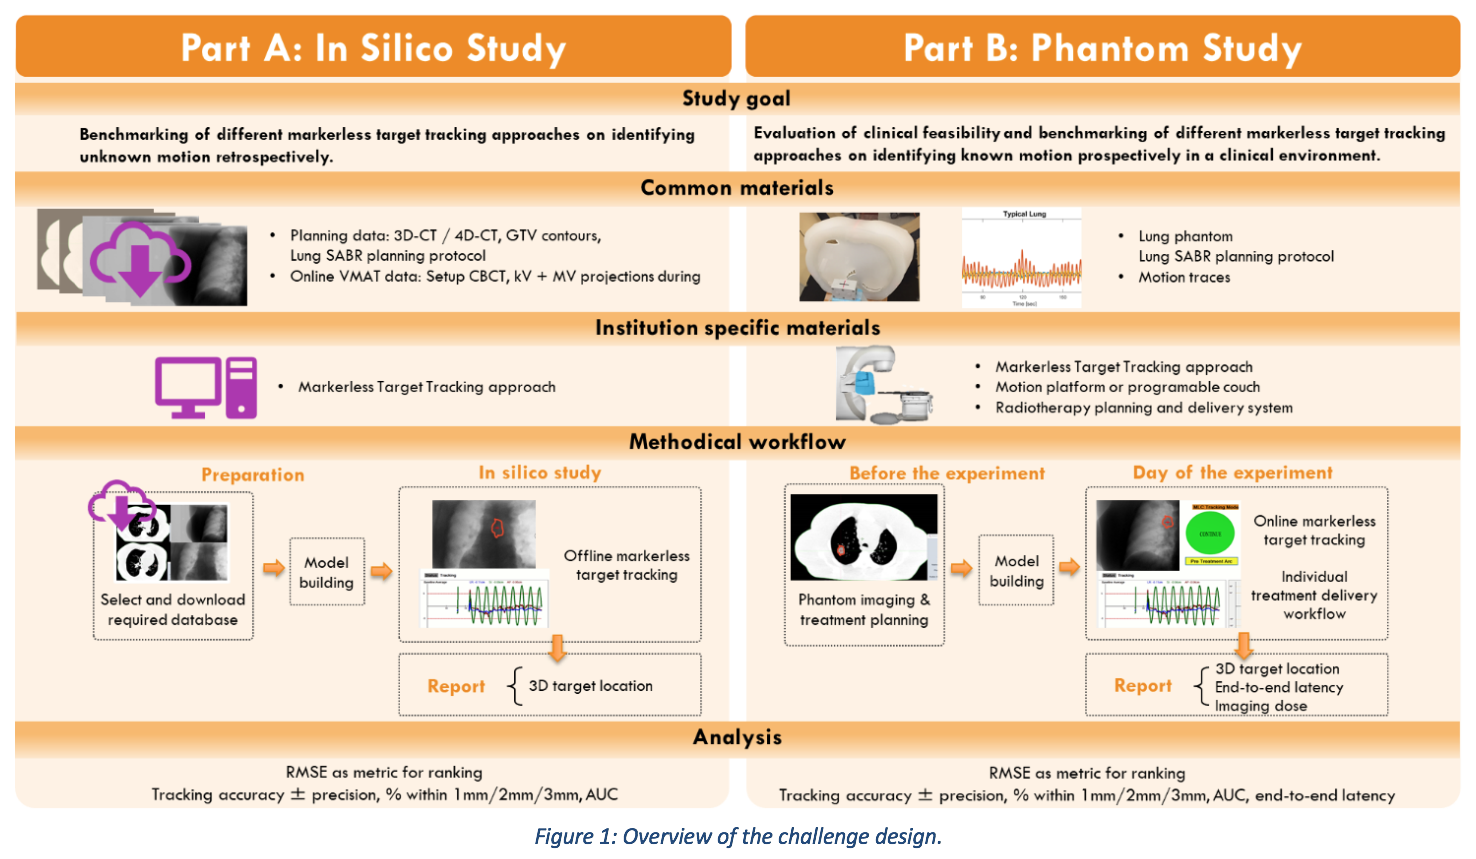

The MATCH challenge stands for Markerless Lung Target Tracking Challenge. The aim is to systematically investigate and benchmark the accuracy of various approaches for lung tumour motion tracking during radiation therapy in both a retrospective simulation study (Part A) and a prospective phantom experiment (Part B).

The MATCH challenge consists of two parts: (Part A) in-silico study based on images with unknown motion and (Part B) experimental phantom measurements with patient-measured motion. The challenge is open to any participant, and participants can complete either one or both parts of the challenge.

Common to both parts of MATCH are a lung phantom3, and a lung SABR planning protocol. The lung phantom is shown in Figure 2. The phantom is anthropomorphically realistic and therefore best suited to the task of evaluating markerless lung target tracking algorithms in a clinical environment. The phantom is a 3D printed anatomy taken from a real patient, including blood vessels, mediastinum with trachea and bony structures. In contrast to a real patient, the phantom can be moved with known displacements, offering a benchmark for the target position. The CT-scan and kV X-ray images of the phantom resemble closely those of a real patient. The phantom includes three targets, two of unit density and one of lower density. The lung SABR planning protocol was taken from RTOG09154, using the 12Gy per fraction arm for expediency of measurements.

Common to both parts of MATCH are a lung phantom3, and a lung SABR planning protocol. The lung phantom is shown in Figure 2. The phantom is anthropomorphically realistic and therefore best suited to the task of evaluating markerless lung target tracking algorithms in a clinical environment. The phantom is a 3D printed anatomy taken from a real patient, including blood vessels, mediastinum with trachea and bony structures. In contrast to a real patient, the phantom can be moved with known displacements, offering a benchmark for the target position. The CT-scan and kV X-ray images of the phantom resemble closely those of a real patient. The phantom includes three targets, two of unit density and one of lower density. The lung SABR planning protocol was taken from RTOG09154, using the 12Gy per fraction arm for expediency of measurements.

The goal of markerless target tracking algorithms is to accurately and precisely reproduce the position of the target with time. For MATCH, the percentage of the values where the algorithm value was within 2mm of the ground truth was selected as a clinically relevant primary ranking metric. Additionally, the accuracy (mean difference in each dimension) and precision (standard deviation of difference in each dimension) will be recorded for each motion trace as well as the percentage of the values within 1 and 3mm of the ground truth.

In-silico study (Part A): The participants are required to submit the tracking algorithm images together with the tracking results to support the integrity of the study.

Phantom study (Part B): The institution-specific materials include the markerless lung target tracking algorithm, a motion-platform or programable couch, a clinical CT scanner, a radiation therapy planning system and a radiation therapy delivery system. As for the experiments the ground truth is known, to support the integrity of the results the CT image set(s), plans, tracking algorithm images, treatment logs, treatment time, motion results, latency and imaging dose are required to be uploaded. Further, the participants may be asked to cover shipping costs for the phantom and additional equipment if required.